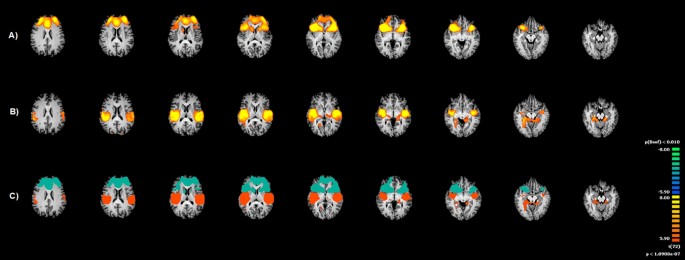

The posterior portion showed functional connectivity with the rostro-dorsal cingulate cortex, the somatosensory regions (S2), the bilateral temporoparietal regions, angular gyri and bilateral thalamus and hypothalamus, extending to the fusiform gyrus, until the extrastriate cortex (Table S2-Supplementary material; Fig. 3).

Insula functional connectivity (FC) patterns during visual sexual stimulation (VSS). Image depicts the functional connectivity patterns maps of the two sub-regions of bilateral Insula (Anterior and Posterior) as assessed with fMRI during VSS. (A) Functional connectivity of Anterior Insula; (B) Functional connectivity of Posterior Insula; (C) Pooled maps (light blue indicates Anterior insula Pattern, while Orange indicates Posterior insula pattern). Maps are overlaid onto a Talairach atlas and in radiological convention with a statistical significance set at p < 0.05, Bonferroni corrected.